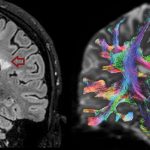

The University of Genoa uses mesenchymal stem cells to treat neurodegenerative diseases

The University of Genoa uses mesenchymal stem cells from bone marrow to treat neurodegenerative diseases. Regenerative medicine represents a challenging area facing one of...